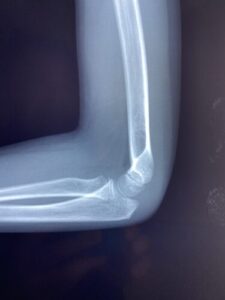

春日部市市民活動センター(肘関節脱臼)

肘関節前方脱臼の1症例について